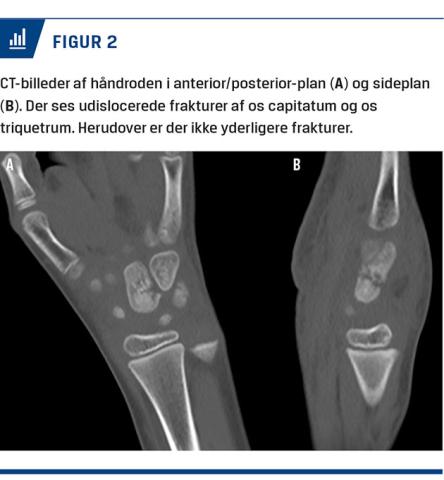

En syvårig dreng blev behandlet på skadestuen efter at have fået klemt venstre hånd mellem kanten af et skolebord og gulvet. Ved en objektiv undersøgelse fandt man misfarvning både dorsalt og volart over håndroden. Han var tydeligt smertepåvirket ved både direkte og indirekte undersøgelse af håndroden. Bevægeligheden i hånden var ophørt pga. smerter. En røntgenoptagelse viste fraktur af os capitatum og os triquetrum (Figur 1). Samme dag blev der foretaget CT af venstre hånd for verificering af diagnosen samt udelukkelse af øvrige frakturer og dislocering med betydning for behandlingen (Figur 2). Frakturerne i os capitatum og os triquetrum var udislocerede og egnede til konservativ behandling. Der blev anlagt en dorsal gipsskinne. Ved ambulant kontrol syv dage posttraumatisk var der bedring smertemæssigt. En røntgenoptagelse viste uændret stilling af frakturerne. Ved ambulant kontrol fire uger efter traumet viste en røntgenoptagelse begyndende kalcifikation af frakturen, klinisk var der smertefrihed. Patienten blev henvist til ergoterapi. Efter seks måneder havde han normal bevægelighed og god kraft i